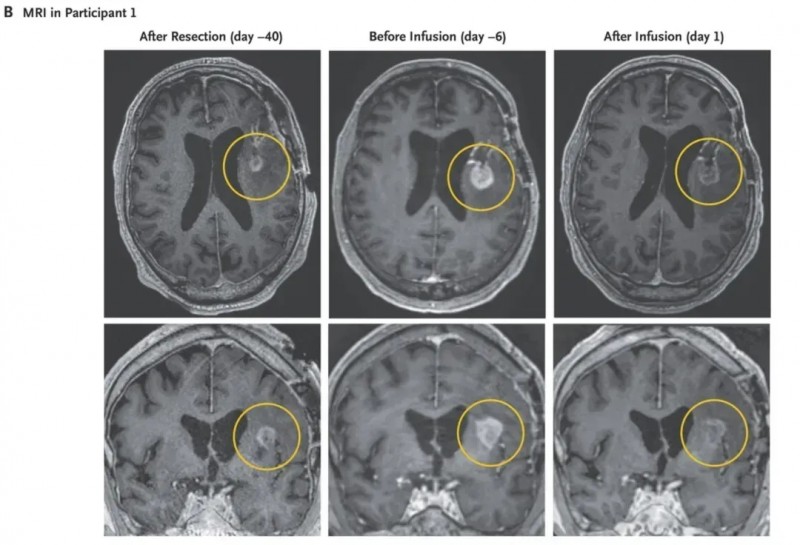

该患者是一名74岁男性,确诊为EGFRv III阳性胶质母细胞瘤,既往接受过开颅手术及放化疗,但效果不佳。CAR-T治疗前6天的MRI提示病情活跃进展,随后患者入组接受CARv3-TEAM-E T细胞治疗。

结果显示:单次输注后,复查MRI提示肿瘤快速消退,疗效持续两周(详见下图);液体活检显示,肿瘤标志物EGFRv III、EGFR显著下降,最终在脑脊液(CSF)样本中未检测到;治疗第72天的肿瘤组织活检结果为EGFRv III阴性。

▲图源“NEJM”,版权归原作者所有,如无意中侵犯了知识产权,请联系我们删除